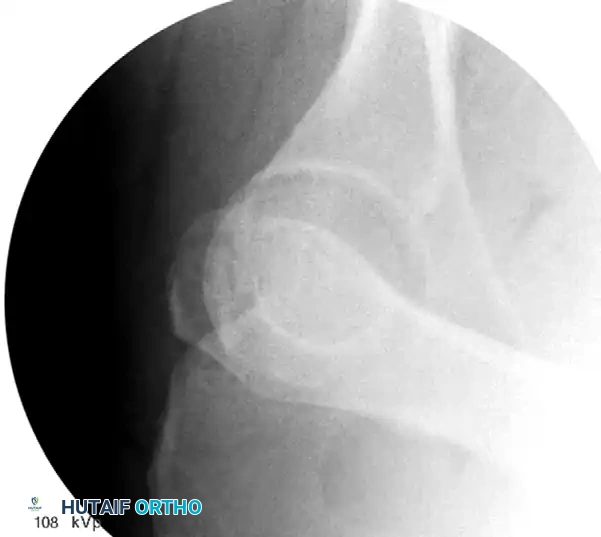

Dynamic Fluoroscopic Stress Testing

Posterior wall fractures demand special consideration. Large fragments (>50% of the posterior wall) invariably lead to posterior hip instability and mandate fixation. However, smaller fragments (<50%) exist in a gray area.

Tornetta popularized dynamic fluoroscopic stress testing for these indeterminate fractures. Under deep sedation or general anesthesia, the patient is positioned supine. The hip is flexed to 90 degrees, and a posteriorly directed axial force is applied while visualizing the joint under fluoroscopy in the obturator oblique view.

If the femoral head subluxates posteriorly, the hip is dynamically unstable, and ORIF is required. If concentric reduction is maintained under stress, the patient can be treated nonoperatively with progressive mobilization.